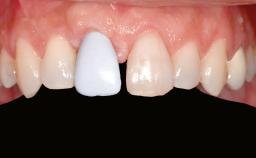

A 45-year-old woman with a completely edentulous maxilla was referred to evaluate the possibility of rehabilitation with an implant-supported prosthesis. This patient was healthy and a non-smoker. She had been wearing a maxillary complete denture opposing a natural mandibular dentition since her twenties. This situation had resulted in progressive resorption of the alveolar ridge, repeatedly creating a need for relining the denture. Twenty years later, despite multiple adaptations and the use of “glues” the denture was unstable and causing the patient psychological and functional discomfort.